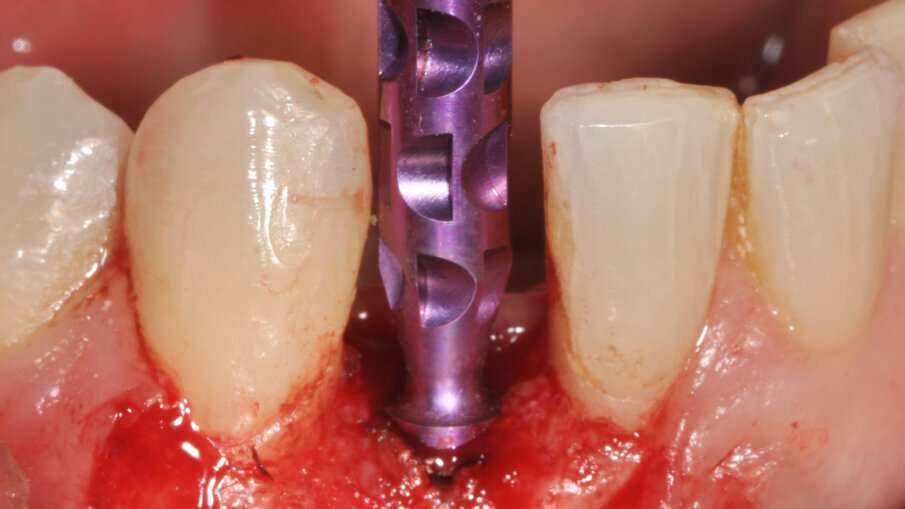

Zavedení implantátu